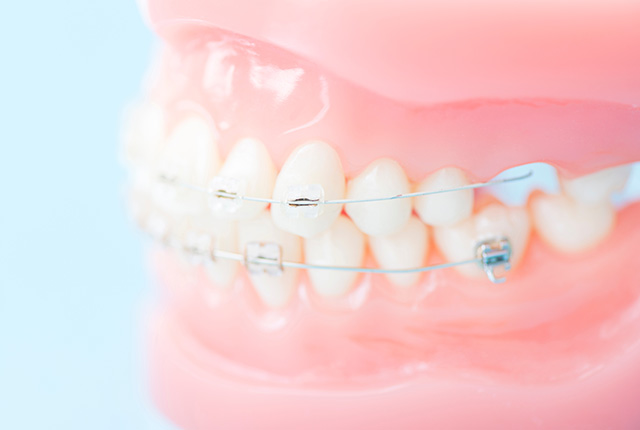

歯の表面にワイヤーとブラケットと呼ばれる固定装置を装着して歯列を整えていく方法で、歯列矯正の中で最も広く行われています。数ミリ単位で歯の移動が可能です。

最近では、歯と同じ色の目立ちにくいブラケットやワイヤーが揃っており、素材を選ぶことで目立ちにくくすることが可能です。